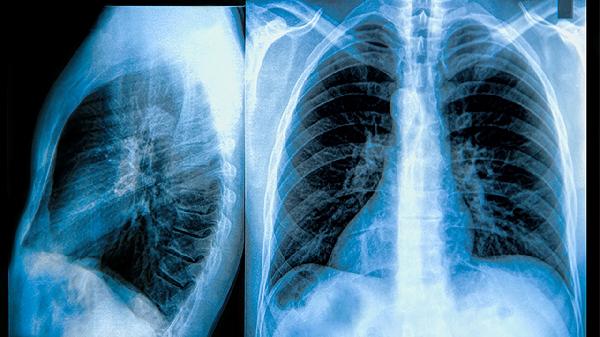

左肺下叶磨玻璃微小结节什么意思

左肺下叶磨玻璃微小结节通常指肺部影像检查中发现的直径小于10毫米的模糊云雾状阴影,可能由炎症、出血、纤维化或早期肿瘤等因素引起。